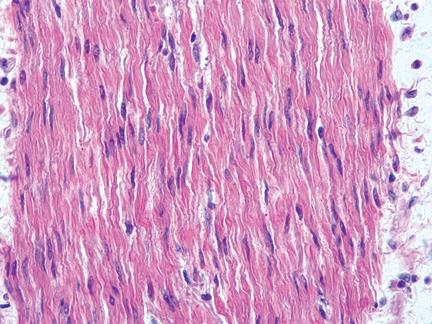

Glad spierweefsel

lange spoelvormige cellen zonder dwarsstreping met 1 centraal gelegen kern, langzame ‘kurkentrekkerachKge’ contractie